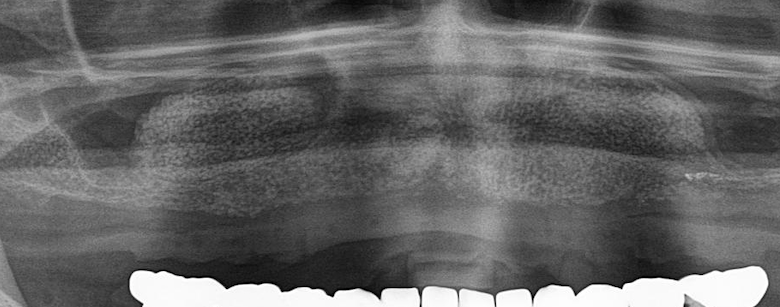

La Sfida del Tempo: Quando La Perdita Ossea Minaccia il Futuro del Sorriso

© Dr.Dr. Schmitz – FreeSmile